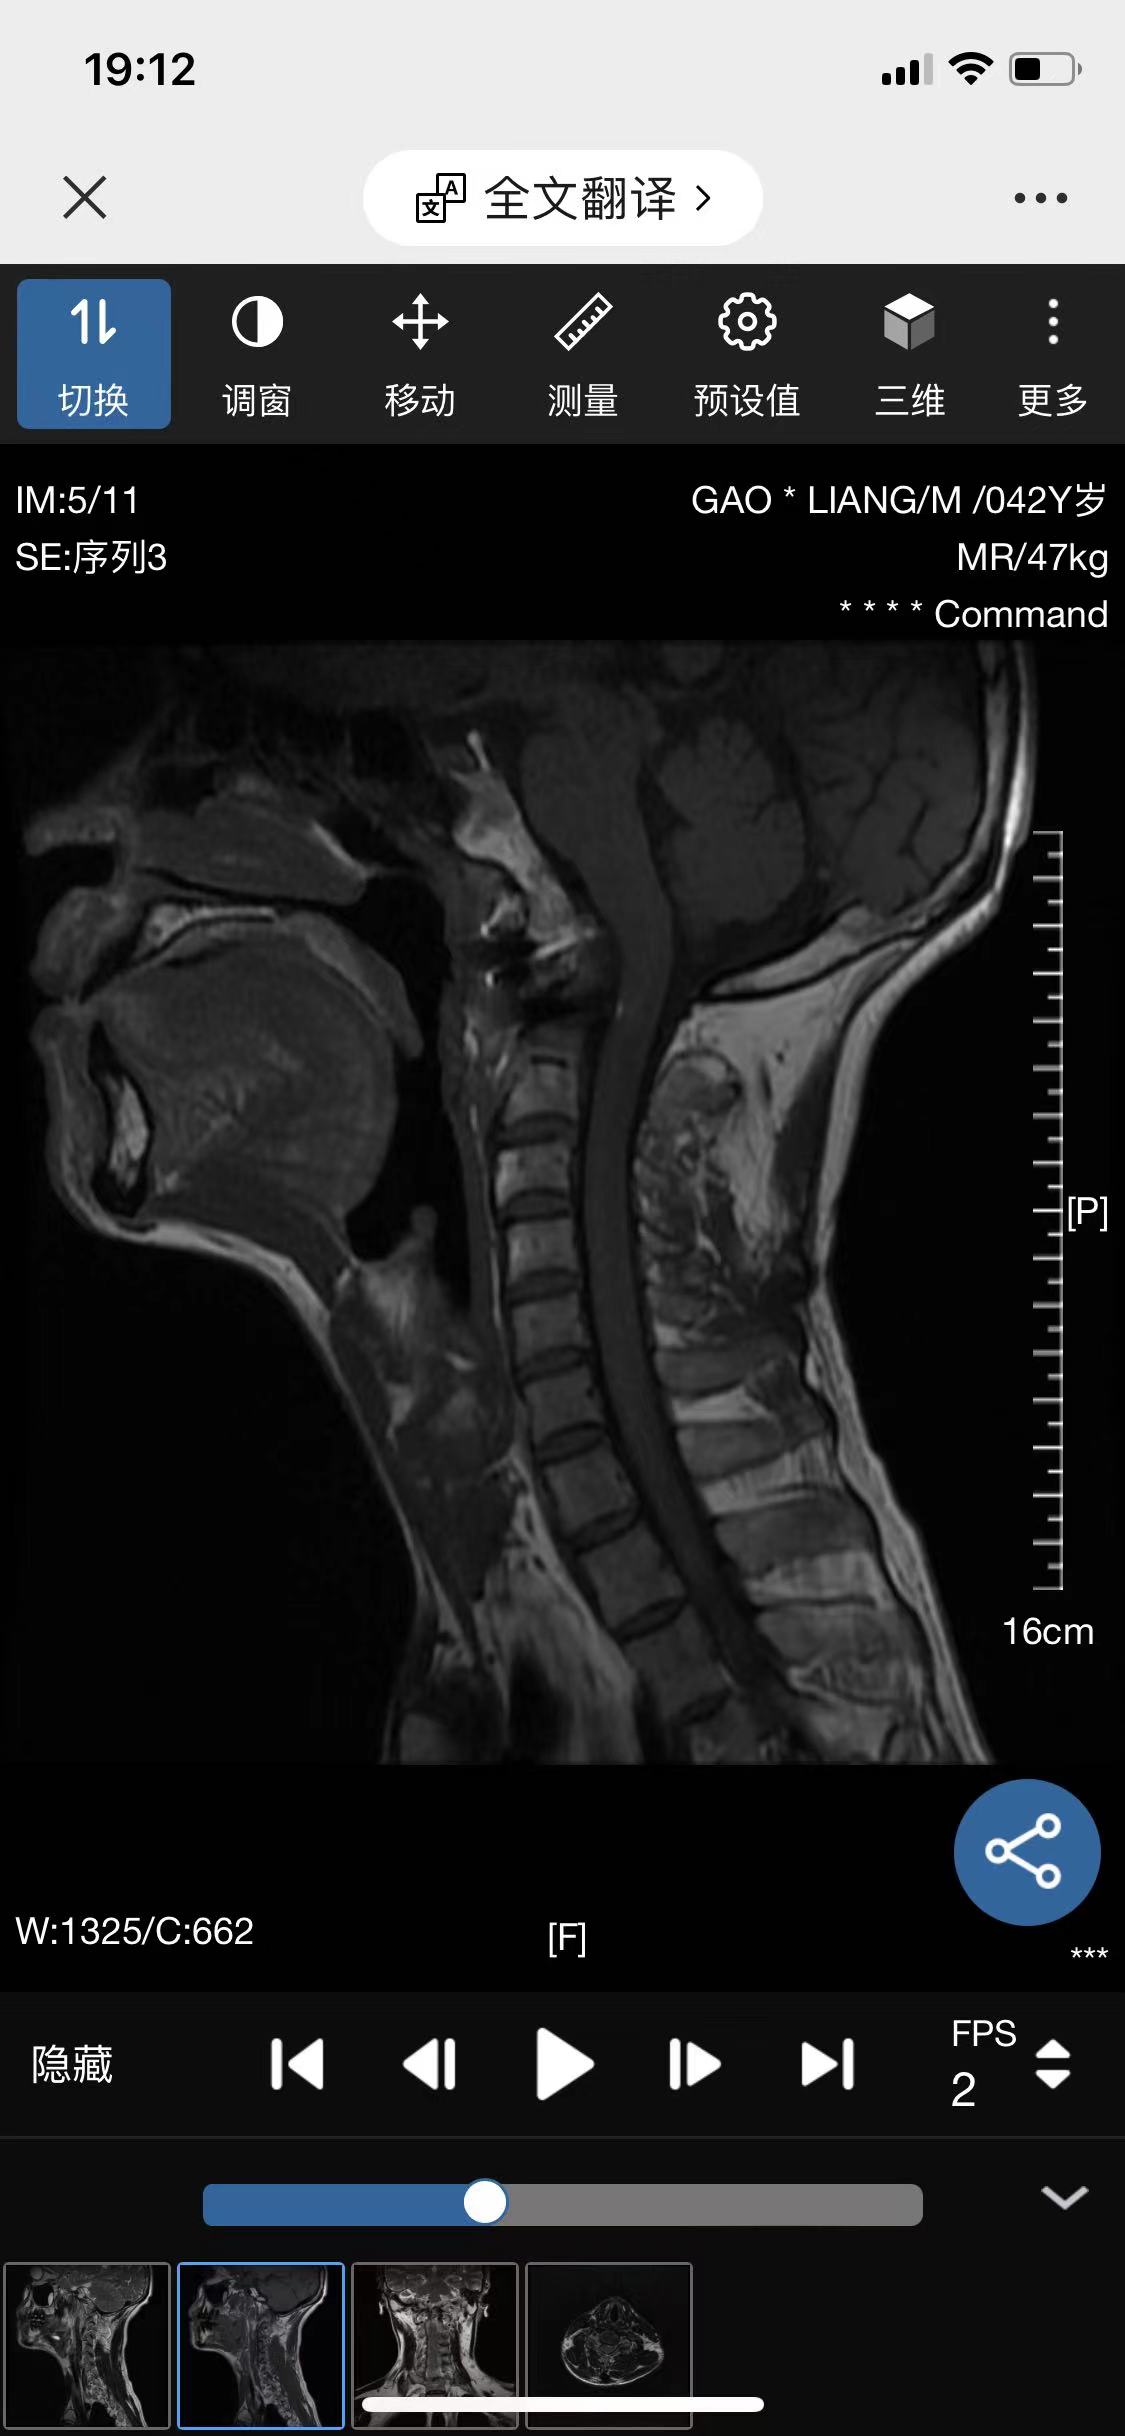

• 诊断:寰枢椎脱位

• 影像:

• 术后影像:

• 2024.04,半年复查。